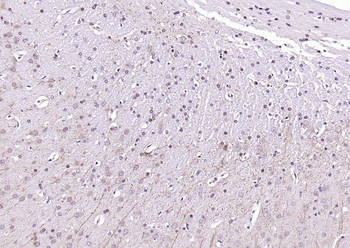

100 μl, 200 μl, 50 μl - LATS2 Rabbit Polyclonal Antibody [orb6306]Featured

IF, IHC-Fr, IHC-P, WB

Human, Mouse, Rat

Bovine, Canine, Equine, Gallus, Rabbit

Rabbit

Polyclonal

Unconjugated

100 μl, 200 μl, 50 μl - Featured